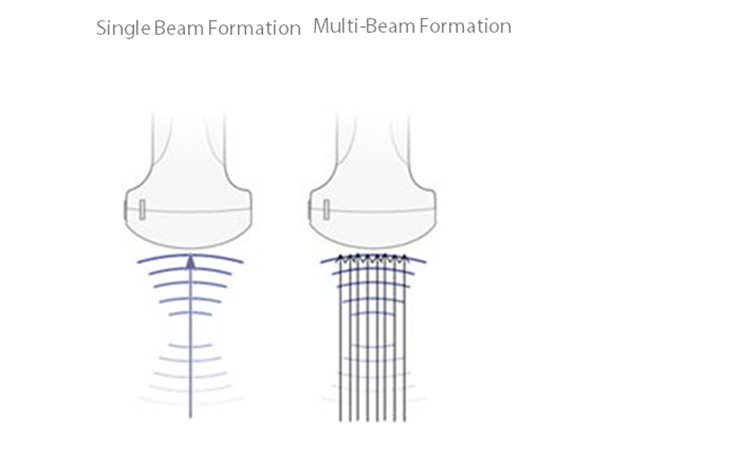

Multi-beam formation

Maximum 8 times tasking for one transmitted beam, resulting in excellent time resolution and higher frame rate.